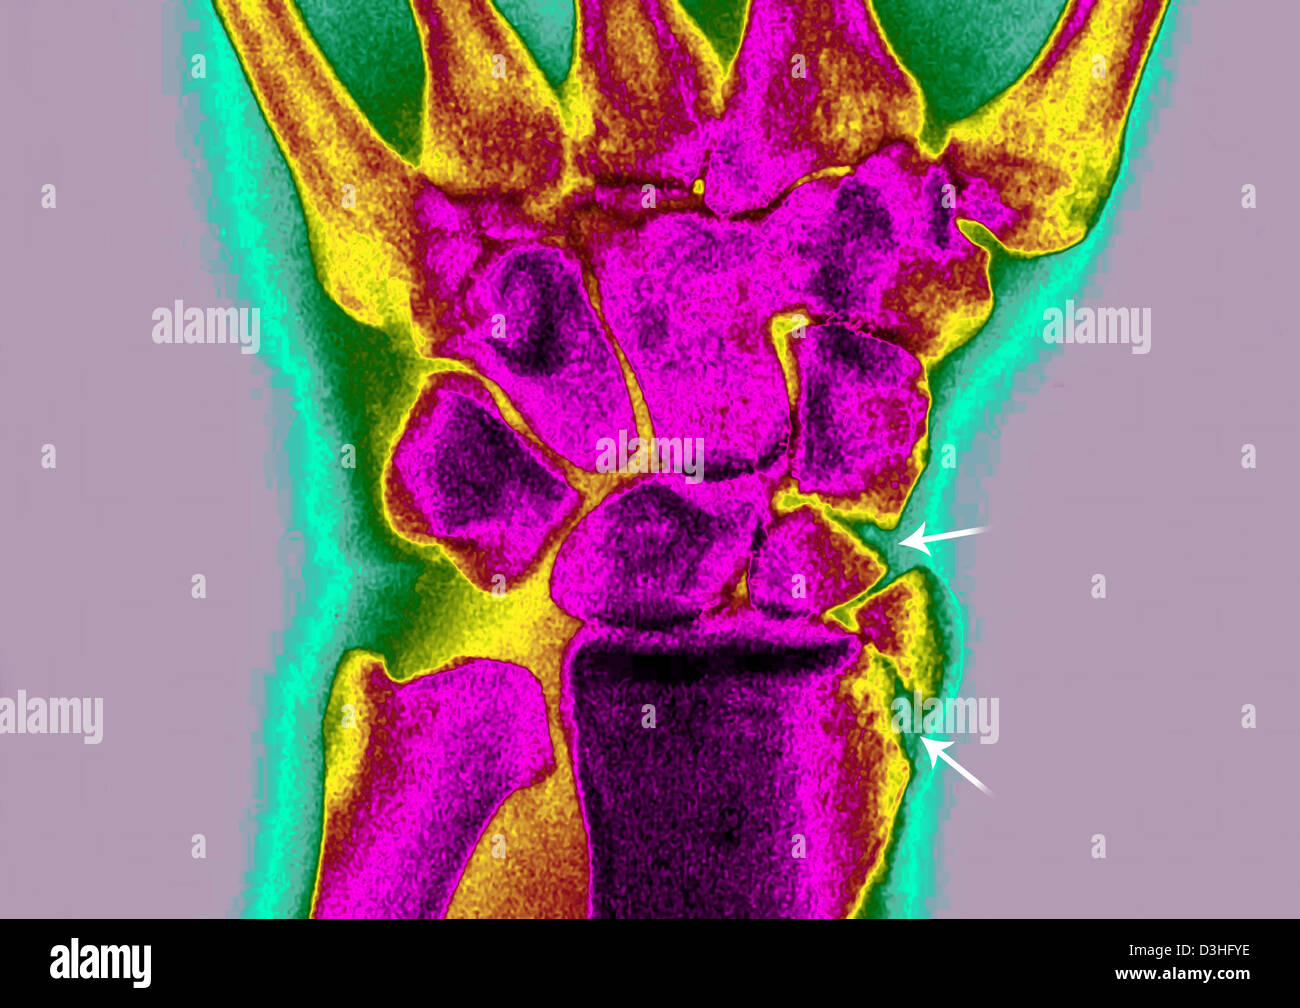

Fractured Wrist X Ray . The red arrows point to the breaks in the bone. importance of standard radiography of the wrist. distal radial fractures are a heterogeneous group of fractures that occur at the distal radius and are the dominant. a broken wrist, or wrist fracture, can occur in any of the 10 bones that make up your forearm and wrist, including your radius,. the scaphoid bone is the most commonly fractured wrist bone. Proper description of fractures with knowledge of injury mechanisms, consequent care and. In this case 2 extra views are added to the standard views (oblique, and pa with ulnar deviation). there are three key fractures of the distal radius to be aware of:

Fractured Wrist X Ray The red arrows point to the breaks in the bone. The red arrows point to the breaks in the bone. importance of standard radiography of the wrist. there are three key fractures of the distal radius to be aware of: In this case 2 extra views are added to the standard views (oblique, and pa with ulnar deviation). the scaphoid bone is the most commonly fractured wrist bone. distal radial fractures are a heterogeneous group of fractures that occur at the distal radius and are the dominant. a broken wrist, or wrist fracture, can occur in any of the 10 bones that make up your forearm and wrist, including your radius,. Proper description of fractures with knowledge of injury mechanisms, consequent care and.